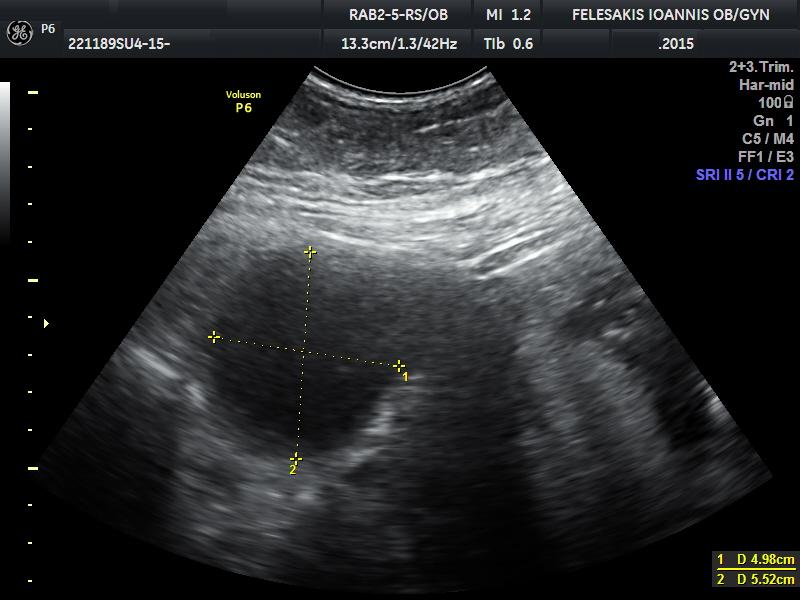

Πώς γίνεται η διάγνωση της νόσου; Την υποψία μας για την ύπαρξη ενδομητρίωσης, μπορούμε να την αντλήσουμε από τη λήψη ενός καλού ιστορικού, τη γυναικολογική εξέταση, τον υπερηχογραφικό έλεγχο των έσω γεννητικών οργάνων της γυναικας και τέλος τη χρήση της μαγνητικής τομογραφίας. Η διενέργεια αιματολογικών εξετάσεων δεν αποδεικνύει την ύπαρξη ενδομητρίωσης. Ο μοναδικός τρόπος για να τεθεί η διάγνωση της πάθησης είναι η διενέργεια λαπαροσκόπησης και η λήψη βιοψιών από τις ύποπτες περιοχές. Η ταξινόμηση της νόσου (στάδιο Ι-ΙV) γίνεται με κριτήριο το μέγεθος των εστιών, την παρουσία και την έκταση των συμφύσεων καθώς επίσης και την επέκταση της νόσου (στις ωοθήκες και σε άλλα όργανα). Η εικόνα της ενδομητρίωσης ποικίλει και, δυστυχώς, δεν έχει βρεθεί τρόπος να συσχετίσουμε τα συμπτώματα της ασθενούς με τον βαθμό ενδομητρίωσης (Ι-ΙV).

Πρέπει να οδηγούμαστε σε χειρουργική επέμβαση κάθε φορά που εμφανίζεται μια ενδομητριωσική κύστη; Υπάρχουν συγκεκριμένα κριτήρια βάσει των οποίων χειρουργούμε μία ενδομητριωσική κύστη και τα οποία ο Γυναικολόγος-Χειρουργός πρέπει να υπολογίσει. Σε πολλές περιπτώσεις άλλωστε, είναι πιο ωφέλιμο για τη γυναίκα να μη χειρουργηθεί.

Ενδομήτριο: Το εσωτερικό στρώμα της μήτρας, αυτό που καλύπτει την εσωτερική της κοιλότητα. Ενδομητρίωμα: Κύστη στην ωοθήκη γεμάτη με αίμα που δημιουργείται όταν η ενδομητρίωση προσβάλλει τις ωοθήκες. Σοκολατοειδής κύστη: Κύστη στην ωοθήκη γεμάτη με αίμα που δημιουργείται όταν η ενδομητρίωση προσβάλλει τις ωοθήκες. Λέγεται σοκολατοειδής γιατί το αίμα που περιέχεται στην κύστη σταδιακά παίρνει καφέ σκούρο χρώμα. Στειρότητα:η απόλυτη βιολογική αδυναμία τεκνοποίησης Υπογονιμότητα: η ακούσια αδυναμία ενός ζευγαριού να επιτύχει σύλληψη και να ολοκληρώσει κύηση μετά από τουλάχιστον ένα έτος τακτικών σεξουαλικών επαφών χωρίς αντισύλληψη.